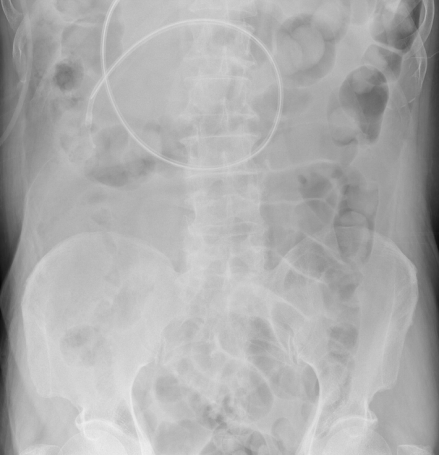

• 胸部X线片:双肺间质性改变,右肺大片实变影(图1)

1  患者胸部X线片